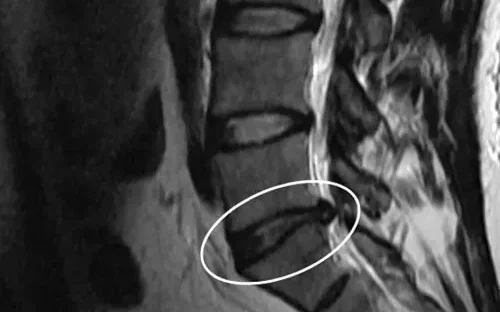

Una hernia discal – también llamado disco herniado, disco desprendido o disco roto – ocurre cuando una presión de la vértebra superior o inferior fuerza a parte o todo el núcleo pulposo a pasar por el annulus que está débil o parcialmente roto. El núcleo pulposo herniado puede oprimir los nervios cercanos al disco, causando mucho dolor.

Las hernias discales suelen ocurrir en la zona inferior de la espina dorsal. Una hernia discal es una de las causas más comunes de dolor de espalda o dolor de piernas (ciática).